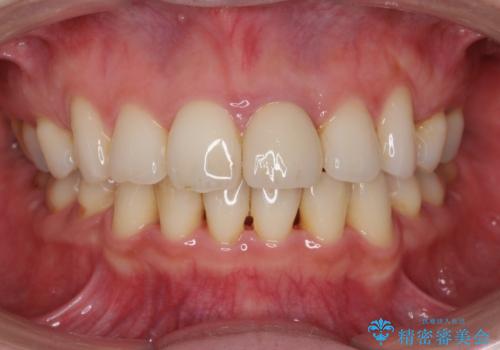

変色してきた前歯をセラミック治療

- 神経の治療をしたまま放置していた歯が、変色してきたので改善したい。と前歯の審美性の改善を求めて来院されました。

根管治療後の歯には部分的な修復処置が為され、変色が進行している状態でした。

ジルコニアクラウンを用いて、自然な色調となるよう治療を計画します。

根管治療は行わず、仮歯・ジルコニアクラウンのみの処置を行い自然な歯に仕上げることができました。